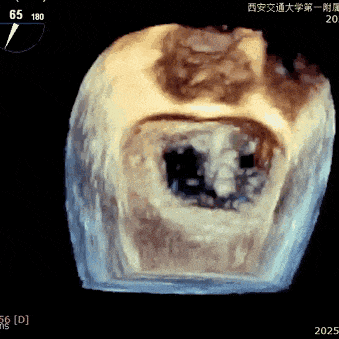

经专家团队评估后决定于2区正中位置先植入一把XTR,植入后评估反流改善情况,如仍有反流,可调整第一把夹子放置于2区偏内,再于第一把夹子外侧植入第二枚夹子,改善对合和反流。

术中在超声引导下完成房间隔穿刺,将第一枚XTR在左房内完成终定位,2偏3区完成植入,夹合效果良好,即刻超声显示轻微反流,完成夹子释放,手术效果良好,手术圆满结束,患者术后6小时即实现床旁活动。